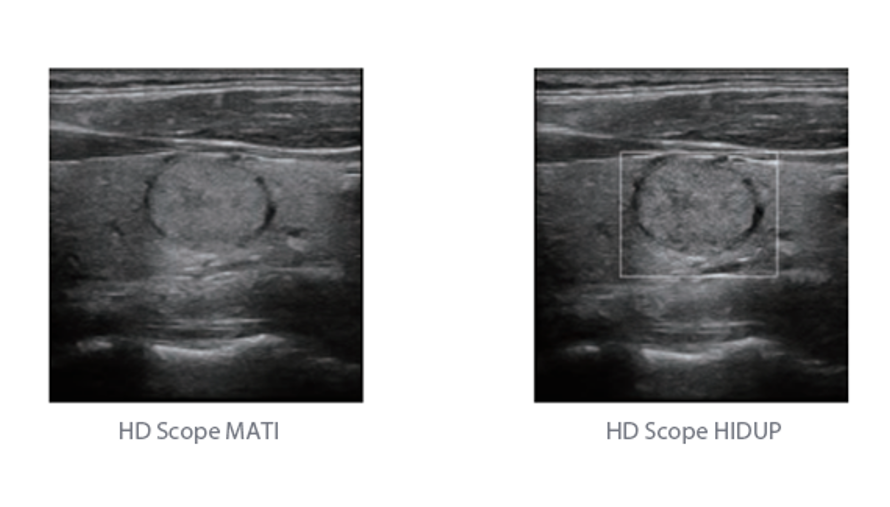

Sejak didirikan, Mindray terus mencari cara baru untuk meningkatkan keandalan diagnostik. Didukung Teknologi ZONE Sonography? terkini, platform ZST+ baru Resona 7 meningkatkan kualitas gambar ultrasound melalui pengambilan zona dan pemrosesan data saluran.

Selain kualitas gambar premium, Resona 7 juga meningkatkan kemampuan penelitian klinis dengan V Flow revolusioner untuk evaluasi hemodinamika vaskular, serta pengambilan penampang tercanggih dari rangkaian data 3D untuk diagnosis CNS pada janin. Kombinasi pengoperasian multisentuh berbasis gerakan yang paling intuitif dengan semua fitur klinis penting membuat Resona 7 menjadi gebrakan baru dalam inovasi ultrasound.